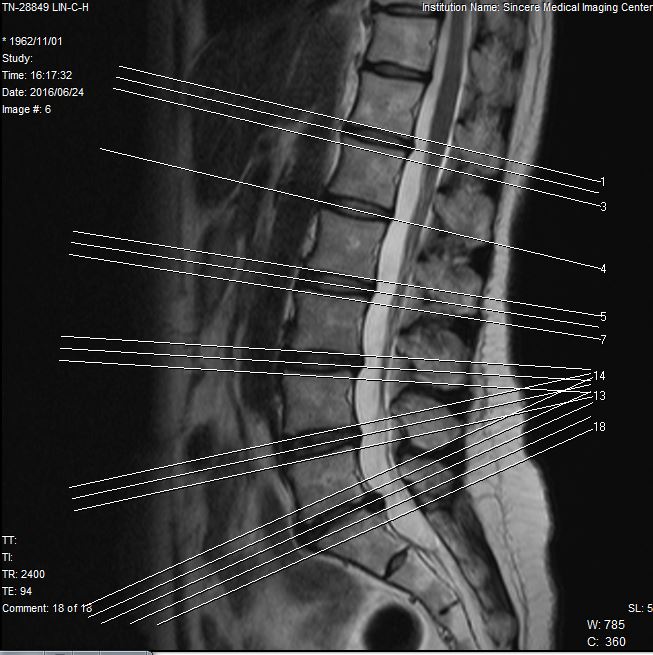

綺華,兩腰臀痛,小腿內側、右腳掌會麻,無法久坐,坐姿超過半小時就不能忍受,出門極度不便,嚴重影響生活。經核磁共振確診,腰椎間盤突出,已壓迫到坐骨神經,醫師建議她開刀處理。

讀者一定會好奇,為何綺華的椎間盤突出,壓迫坐骨神經,我們確能在未開刀下處理此問題?答案在於,坐骨神經固然有骨性組織的壓迫,但在漫漫長路中,還是有很多軟組織會壓迫到它,開刀固然能夠解決骨性組織問題,但對於軟組織壓迫,是毫無助益的。甚至,開刀的傷口,在癒合時所形成的斑痕組織,又可能造成更大的壓迫。

圓針藉由切割剷撥方式,能解決軟組織的問題,很多時候,骨性組織問題看起來雖明顯,但未必是疼痛的主要問題點,甚至連問題點都稱不上,我們以圓針鬆解坐骨神經路徑上所有緊僵壓迫的筋膜、肌肉等軟組織,使其張力消除,雖然不見得能解決所有問題,但大部分問題往往也能因此改善。